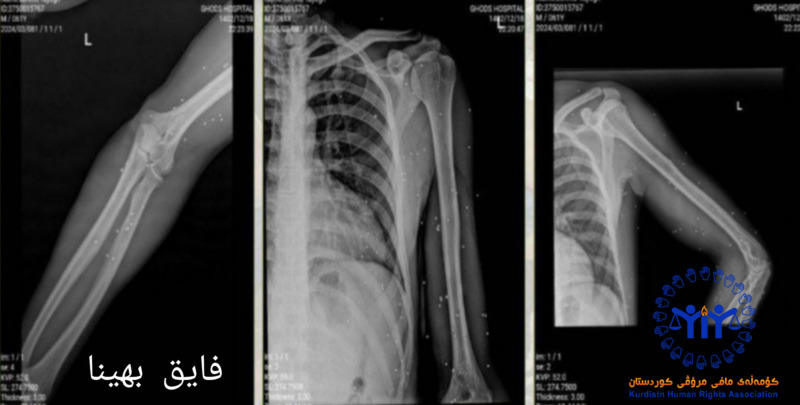

لازم به ذکر است، بر اساس عکس رادیولوژی و مدارک پزشکی این شهروند از ناحیه چپ بدن مورد اصابت بیش از ۵۰ عدد گلوله ساچمه قرار گرفته، این شهروند جهت درمان به مراکز درمانی انتقال داده شده است.